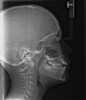

Instinctively, clinicians have concentrated on the mandible when discussing airway dimensions. However, the maxilla appears to be the more important arch in determining upper airway dimensions in OSA patients.45 The distance from A point (most posterior point in the concavity of the anterior maxilla) to Porion vertical (vertical line drawn from the most superior part of the external auditory meatus) was the most contributory cephalometric marker for airway patency. Appropriate positioning of the maxilla opens the velopharyngeal and orophayngeal airways. Additionally, proper maxillary positioning enhances mandibular growth. Thus, the lack of facial muscle activity and ideal tongue tone constrains the premaxilla, producing an abnormal airway dimension and amplifying the threat of SDB.

Tonsils and adenoids should be judged against the relative size of the airway rather than the absolute size of the lymphoid tissue46 (Figure 5 and Figure 6). Adenoids are located at the posterior of the nasal cavity on the roof of the nasopharynx (Figure 7). The normal distance from the adenoids to the soft palate for an acceptable airway should be at least 12 mm. For each millimeter decrease, the odds of the child snoring increase 1.61 times. Mouth breathers typically show a smaller upper airway dimension as well.47 The adenoid and tonsillar obstruction creates the trigger, but the deviate facial and neck muscle recruitment and tongue hypotonia cause the maldevelopment.48

The point of obstruction tends to determine the type of skeletal impact. Nasal obstruction from enlarged turbinates, blocked ostium maxillare, deviated septum, or nasal valve stenosis creates Angle occlusions of Class I, II, and III equally (Figure 8). The maxilla in these cases is positioned posteriorly and the mandible is posterior-inferior. The facial type is most commonly dolicocephalic. Blockage of the airway predominately by the adenoids will create growth patterns that yield mostly Class II occlusions and anterior open bite with both jaws located posterior-inferiorly. Facial type is again dolicocephalic with the typical long-thin “adenoidal” face49 (Figure 9 through Figure 12). If the tonsillar tissue is responsible for the airway obstruction, the tongue will have an abnormal resting posture. Class III occlusions will be more common with the maxilla normal or posterior placed (Figure 13 through 15). The tongue may direct the mandible anteriorly or, because the tongue is not in the roof of the mouth driving A point anterior, the maxilla will become bimaxillary retrusive.50 In some cases, the anterior posture of the tongue will create an open bite. This is incorrectly referred to as a tongue thrust. The impact from a thrust does not alter the tooth position. Long-term, low forces cause tooth movement. The posture of the tongue against or between the anterior teeth due to the excessive tonsillar size creates the open bite (Figure 16 and Figure 17). Facial types in this group are more brachyfacial. Lastly, if the airway is blocked through a combination of factors, the Angle classification will be either Class II or III. The maxilla will be in a normal location and the mandible will be the affected arch (Figure 18). These craniofacial changes are not restricted to OSA; all SDB will create unique alterations depending on the patient compensation. Children with UARS have been reported to display high, narrow palates, dolicofacial form, and a Class II malocclusion, indicative of largely adenoidal blockage.51

Dentists identifying craniofacial changes early in development may resolve the malocclusion by simply referring for adenotonsillectomy (T&A). The impact of T&A on the pediatric immune system is controversial. A recent 5-year longitudinal, prospective study demonstrated that adenotonsillectomy does not pose adverse short- or long-term impact on the cellular or humoral immunity.52 Cephalametric changes (eg, posterior incline to the mandible, anterior incline to the maxilla, longer anterior and shorter posterior face height, and upper and lower teeth more retroclined than a normal matched control) were detected in 5-year-old subjects with adenoid-induced OSA.53 T&A resolved the OSA in all subjects. At the 5-year recall, cephalometric evaluation demonstrated that the mandibular plane angle and incisor relationship was similar to the control. Early resolution of the SDB allowed time for the proper use of the oral-facial and tongue muscles. Closed mouth breathing with the tongue in the roof of the mouth directed ideal growth.